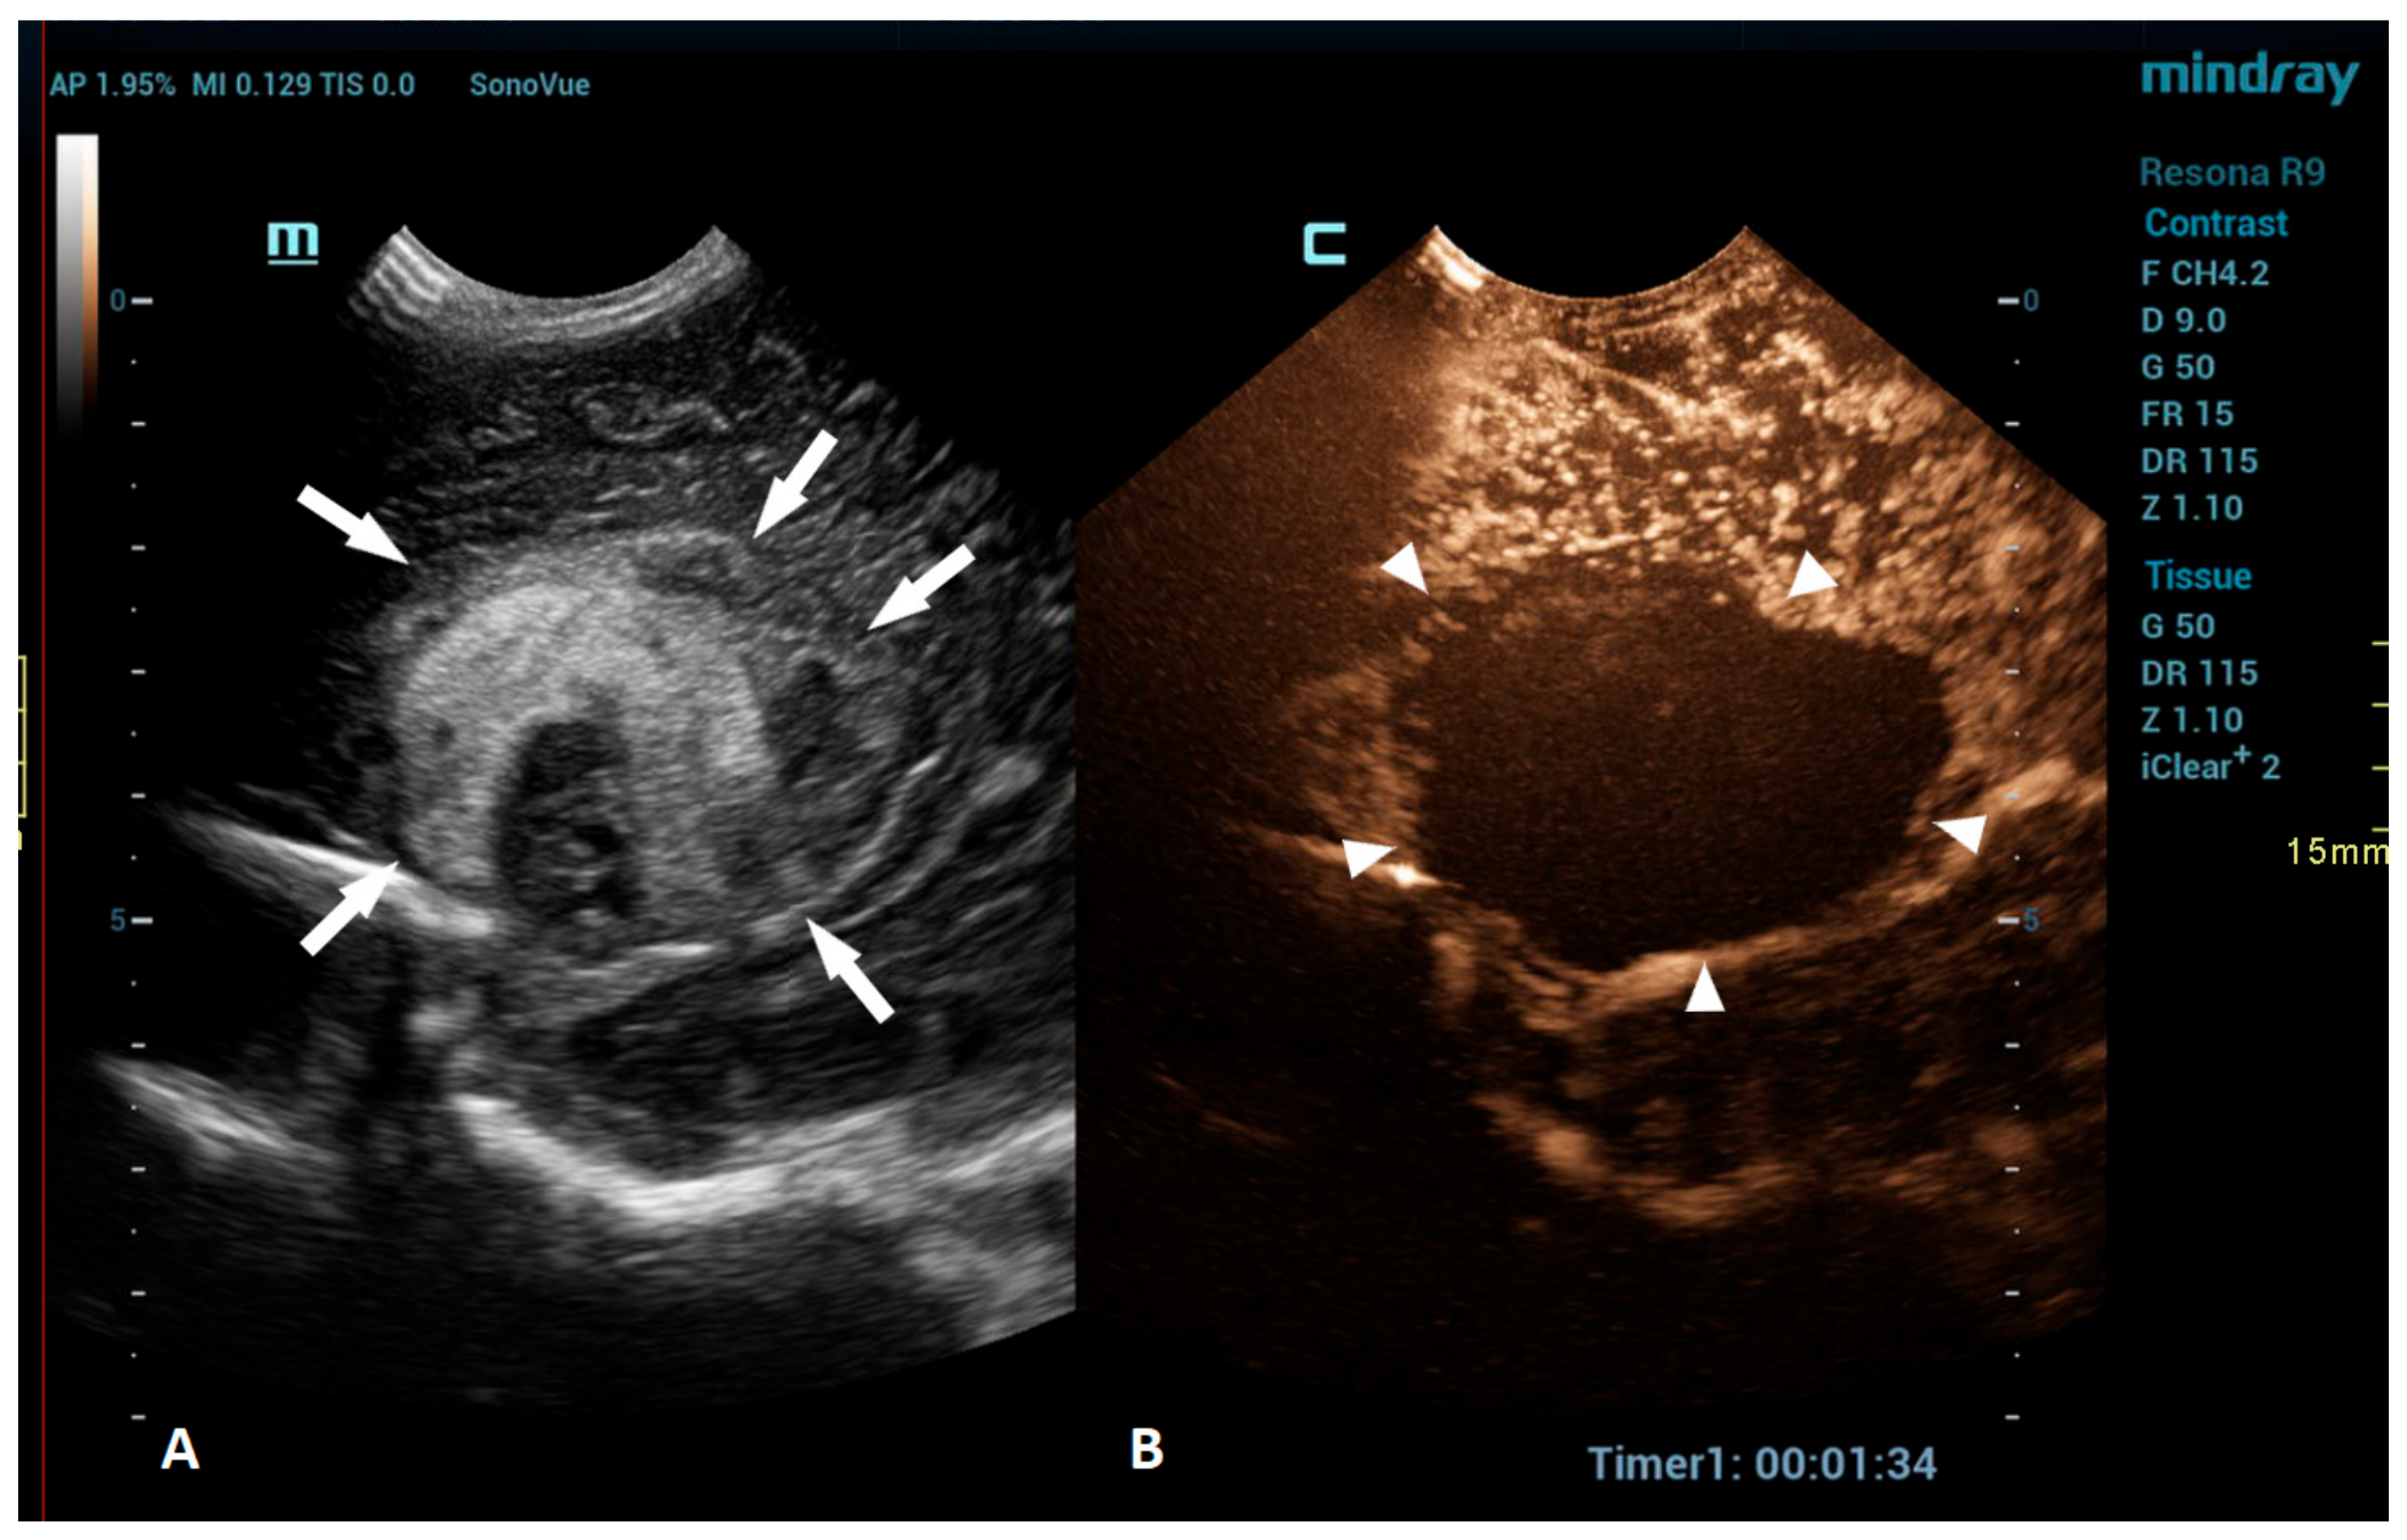

Figure 3.

A 1-day-old boy who presented with apnea. (A) The sagittal grayscale ultrasound brain image reveals a heterogeneous lesion (arrows) in the right frontotemporal region. (B) The sagittal CEUS image confirms avascularity of the lesion (arrowheads), consistent with the hemorrhage, and no obvious vascular malformation.

An intracranial hemorrhage (ICH) in the neonatal period is a serious clinical problem and an important cause of morbidity and mortality [52]. Many inherited and acquired disorders may cause a neonatal ICH. However, in a large proportion of cases, the etiology cannot be identified [53]. Full-term neonates with an ICH commonly present with clinical features, such as apnea, bradycardia, and seizures [54,55,56]. With improvements in diagnostic imaging in recent years, even a small ICH is being increasingly recognized. The true incidence of ICHs is likely higher than reported, as only a fraction of infants with an ICH present with clinical features [54]. Diagnostic imaging plays an important role in the detection of ICHs. A cranial US is a first-line modality for the evaluation of a neonate suspected of having an ICH. USs are a highly sensitive and dependable tool for assessing the ventricular system and central brain structures. It is highly effective in detecting germinal matrix hemorrhages, intraventricular hemorrhages, and hemorrhages in central brain structures [53]. However, a limitation of the US is its poor visualization of the peripheral and deep brain regions. Using additional acoustic windows, like the mastoid fontanelle, posterior fontanelle, or foramen magnum, can help overcome these limitations. In cases where more detailed information about ICH lesions is necessary, or if there are still suspicions despite there being normal cranial US results, MRI is the preferred imaging method. Unlike USs, MRI can capture images of the entire brain, as it is not limited by acoustic windows. Furthermore, MRI has the ability to utilize hemorrhage-sensitive sequences like susceptibility-weighted imaging (SWI), which is unparalleled in its sensitivity in detecting hemorrhages [57]. Therefore, MRI is considered the gold standard for further imaging when more comprehensive information is needed. However, there are also limitations to the use of MRI. In the neonatal period, MRI typically requires general anesthesia. Additionally, patients with a suspected ICH are often located in the neonatal intensive care unit, and they may be difficult to move to an MRI machine in another department; therefore, MRI is not always feasible. A CEUS is an emerging radiological modality that could prove especially useful in the detection of ICHs. The CEUS is a technique based on the vascularity and perfusion of the observed organ. As such, it may be an ideal tool to detect areas without perfusion, such as hemorrhages. The areas with normal perfusion greatly differ in terms of signal from that of the areas without perfusion, which should also improve the visualization of such areas in the peripheral and deep regions of the brain. Several recent studies have already described cases of ICHs that were more accurately diagnosed using CEUSs in comparison to that using MRI [20,51]. CEUS shows preserved cerebral perfusion around the hemorrhage (i.e., the presence of microbubbles within the brain) and the region of heterogeneous hypoperfusion in the affected area of the brain with the hypoechoic hemorrhagic core (i.e., no microbubbles entering the hematoma) (Figure 3).